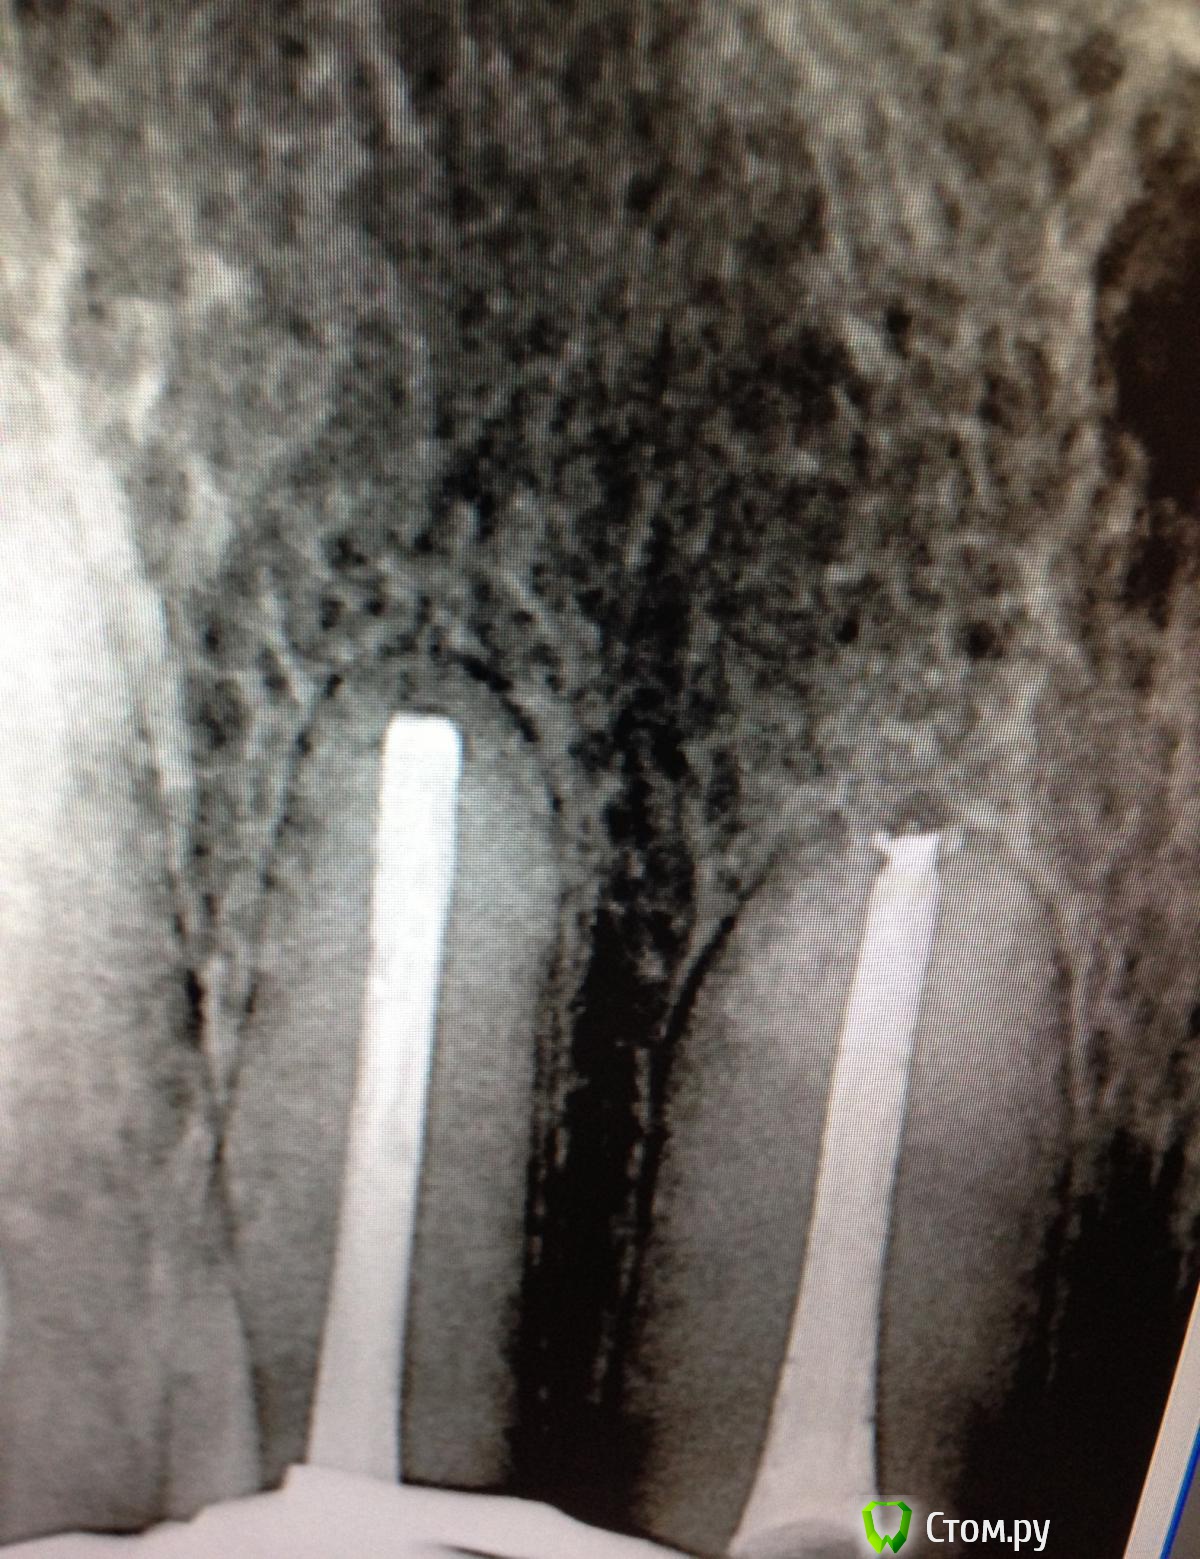

SSTi Опубликовано 16 октября, 2014 Автор Поделиться Опубликовано 16 октября, 2014 46. Пульпит. По приказу свыше. Убрал бломбу, каривус. Коффер. Открываемся. Полость склерозирована. В ней- дентикль. Уз убрал. В каналы только десятка заходит. Долго долго расширял. Очень долго. Дистальные 25.06, 30.04 профайл. Медиальные 20.06, 25.04. Ирригация стандартная. И очень обильная. Дистальные сходится. П.с. Про кость знаю. 5 Ссылка на комментарий